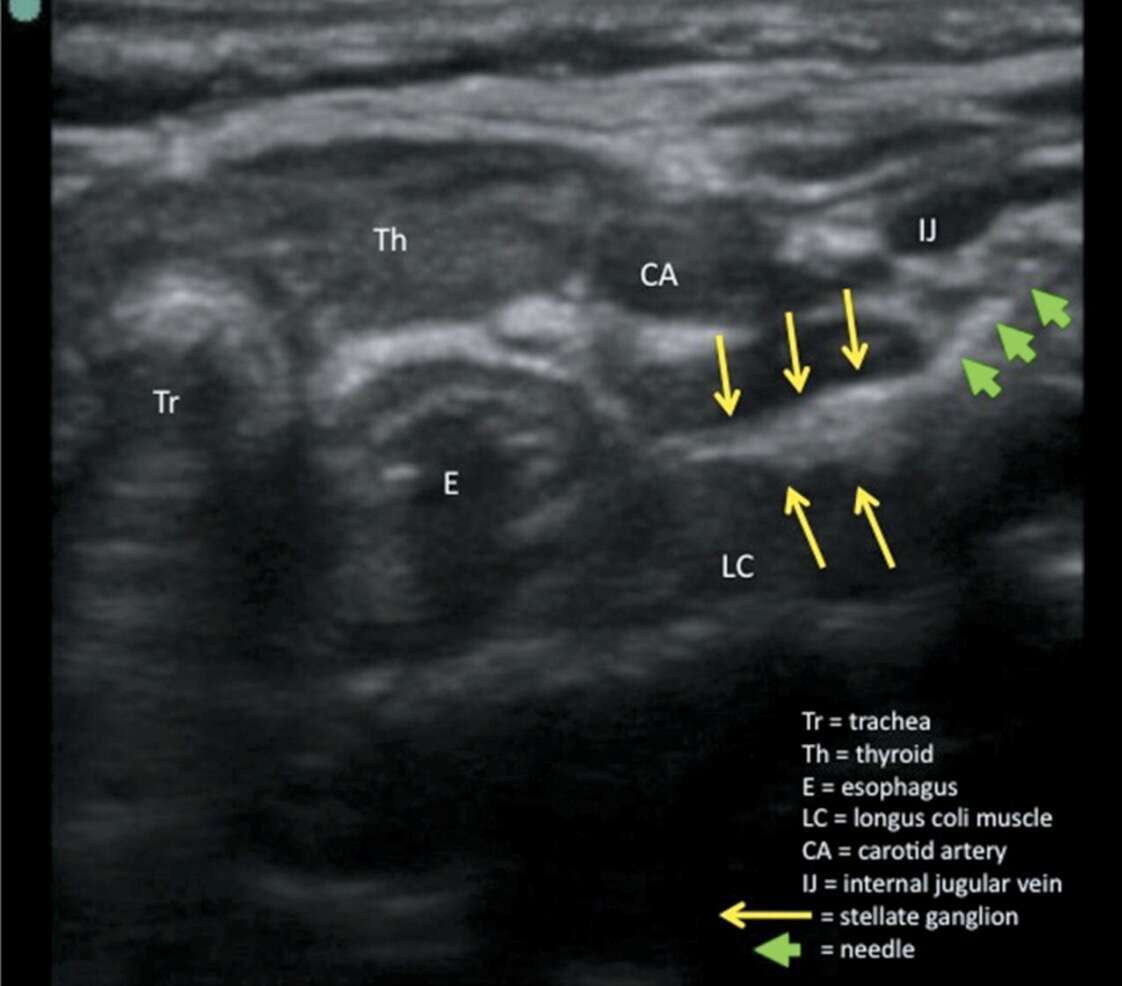

-At this stage it was decided to do stellate ganglion block to tide over the unrelenting VT storm.

-Initially Left stellate ganglion block with 10 ml of 0.25% bupivacaine under ultrasound guidance was done and there was substantial decrease in the VT episodes.

-Subsequently successful Right stellate ganglion block was done with 10 ml of 0.25% bupivacaine under ultrasound guidance.